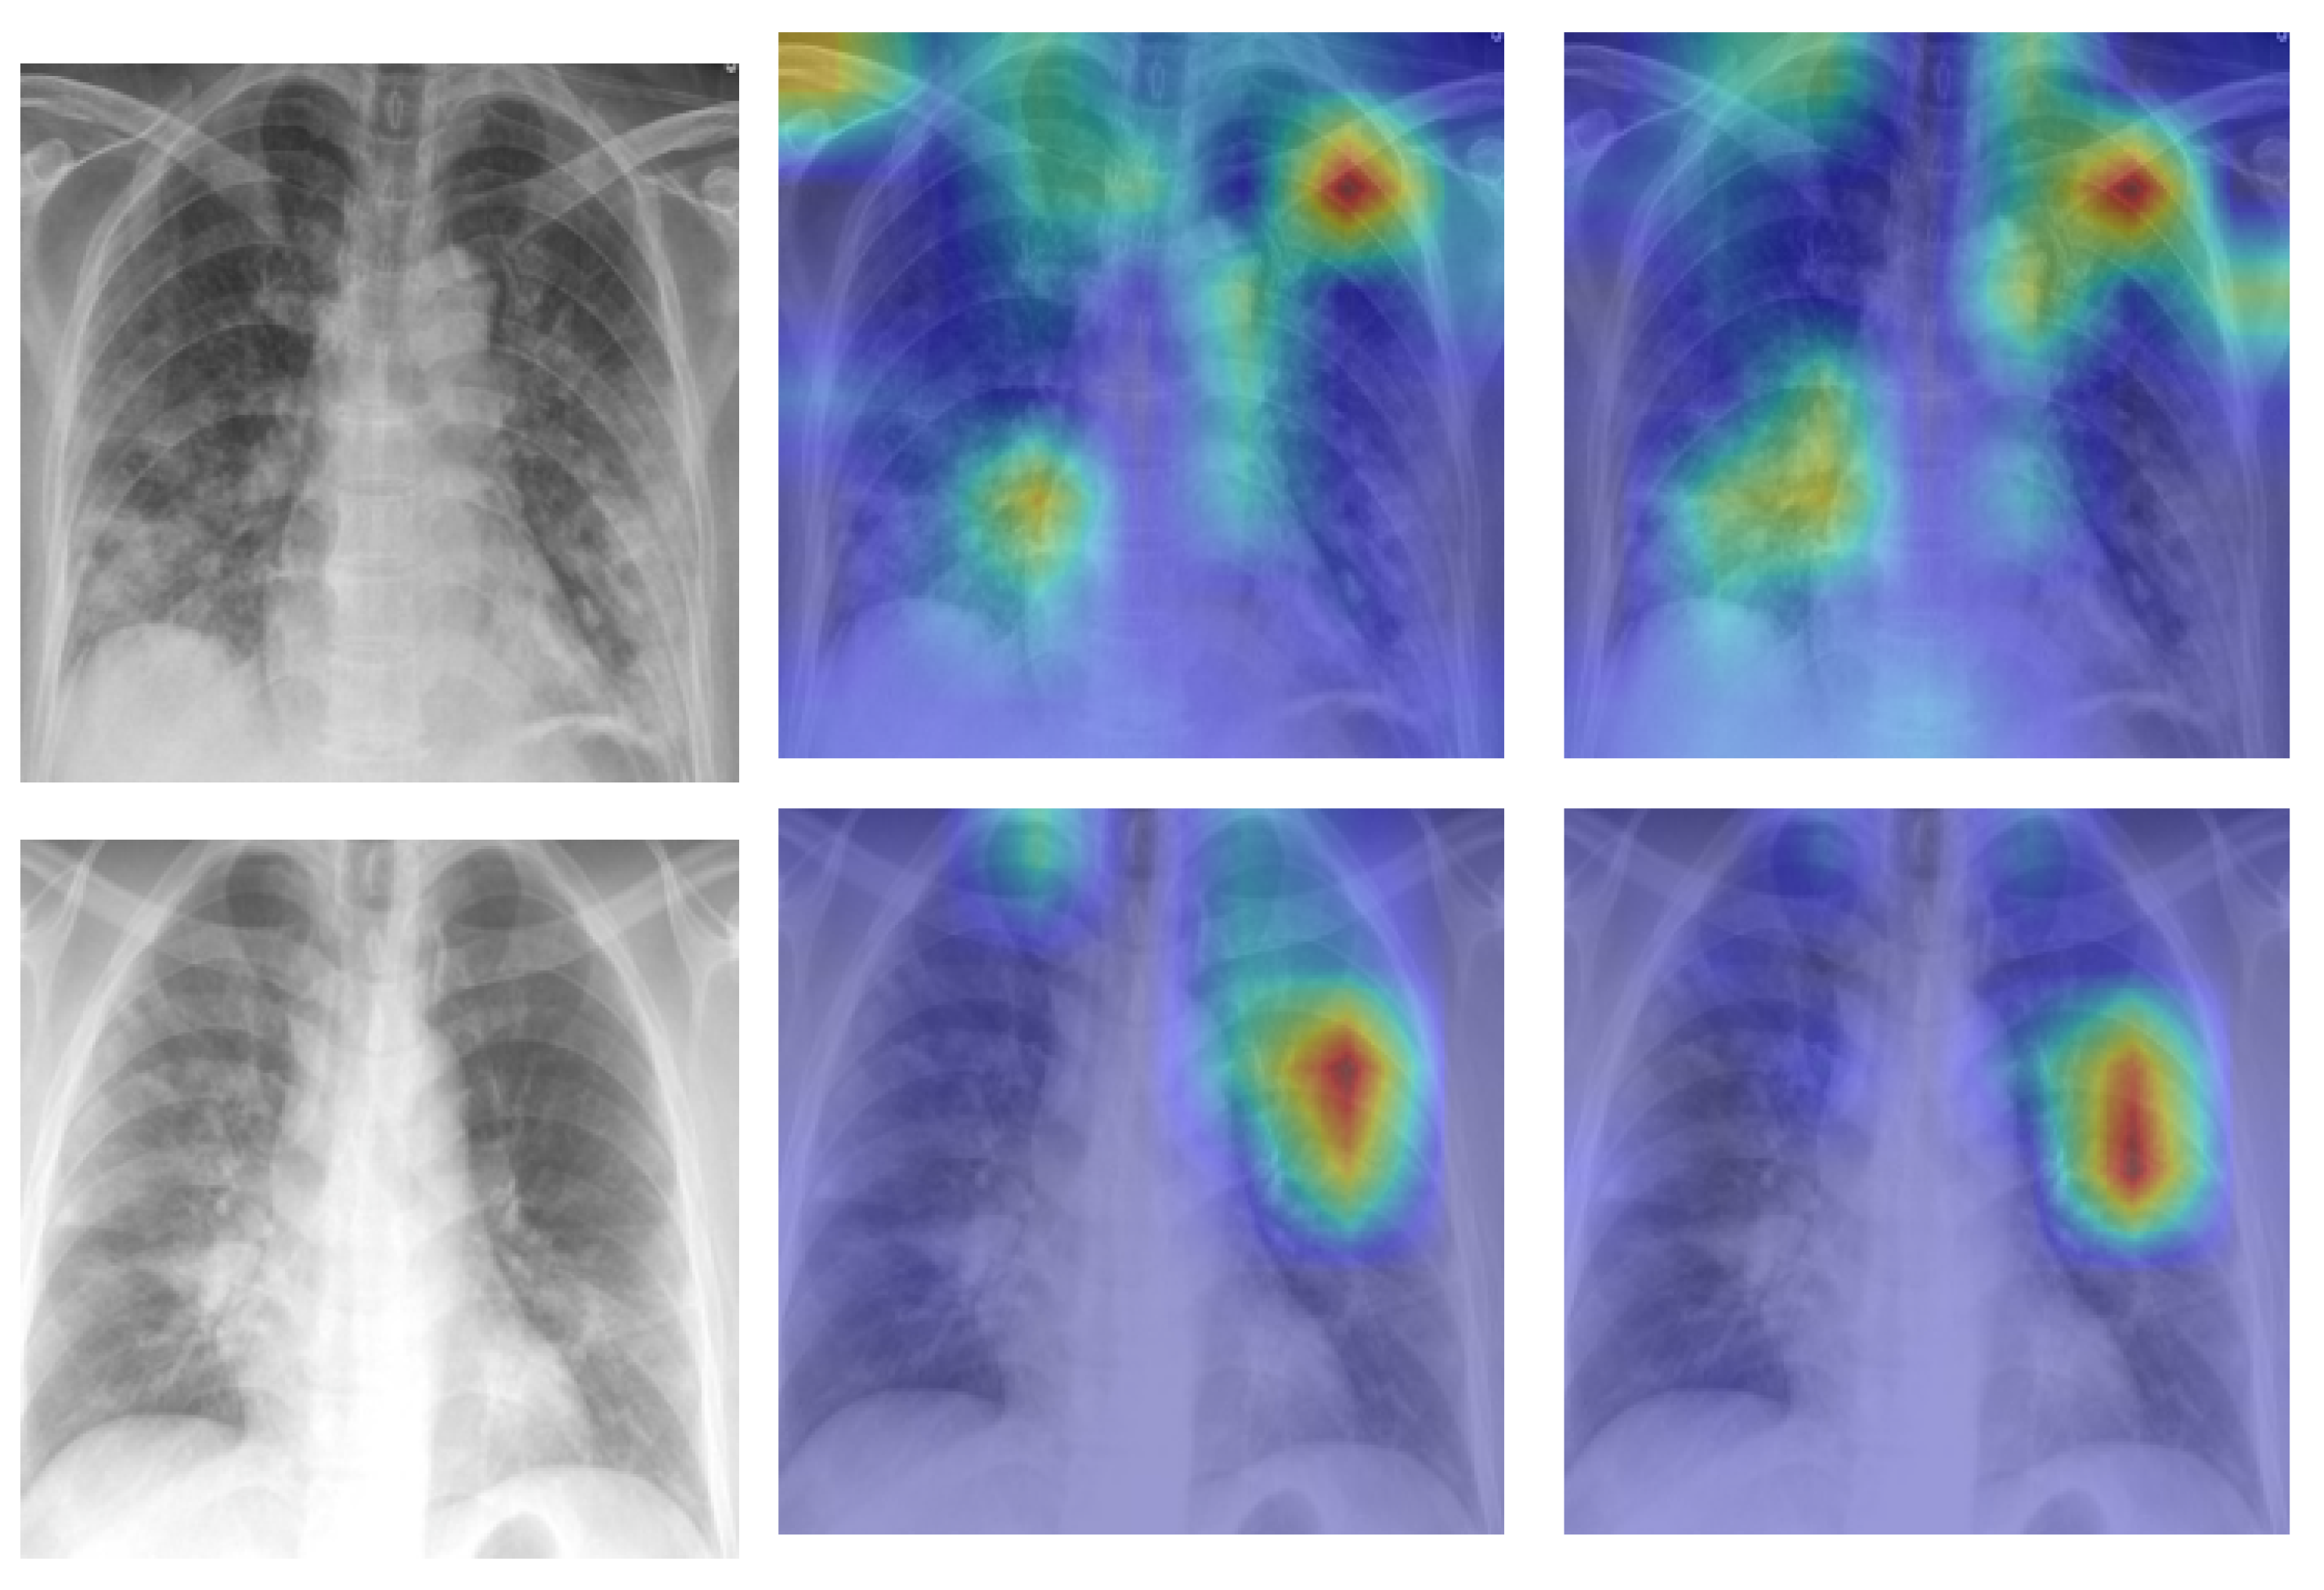

Figure 2 shows examples of SIIM-COVID-19 and RSNA CXR images.

Figure 2. Examples of CXR images; SIIM-COVID-19: (a,b) and RSNA: (c,d).